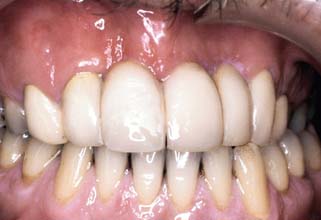

Unfortunately, periodontal disease often occurs after placement of fixed prostheses,26 especially where the cavosurface margin has been placed subgingivally27-29 or the prosthesis is overcontoured.30 Inflammation is more severe with poorly fitting restorations31 (Fig. 32-12), but even “perfect” margins have been associated with periodontitis.32 At recall appointments, particular attention is given to sulcular hemorrhage, furcation involvement, and calculus formation as early signs of periodontal disease. Improperly contoured restorations should be recontoured or replaced.

Fig. 32-12 Periodontal failure resulting from defective fixed prostheses. A, Inadequate margins and contour. B, Appearance before surgery. C, Flap reflected. D, Appearance after surgical recontouring. E, Radiograph of new cast restorations. F, Replacement restorations.

(Courtesy of Dr. C. L. Politis.)